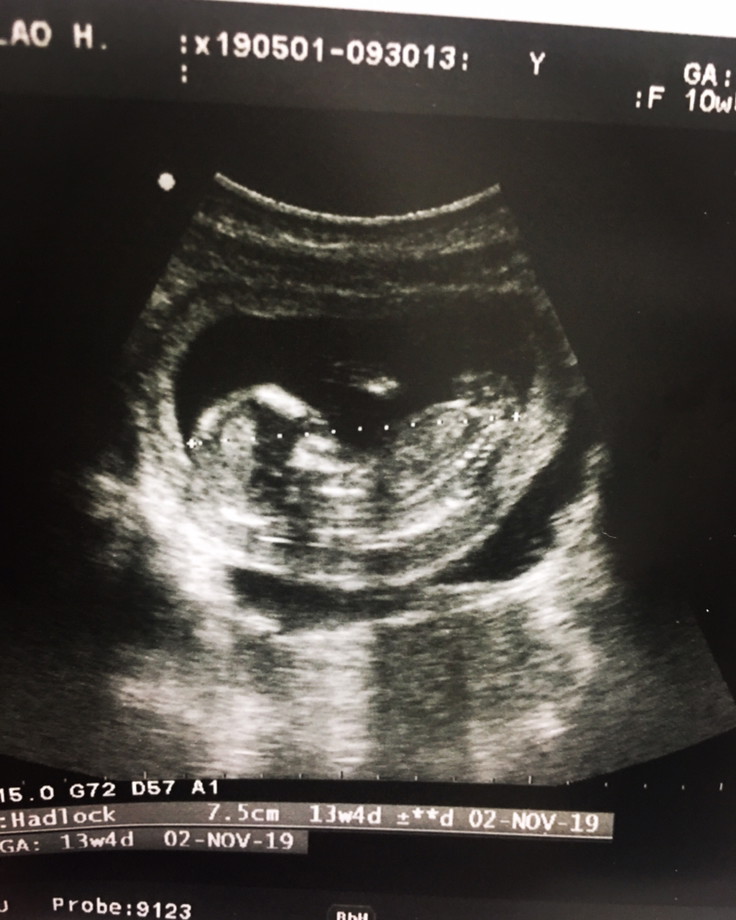

13สัปดา หนูจมูกโด่งไหมค่ะ ❤️❤️❤️🐷👼🏻👼🏻